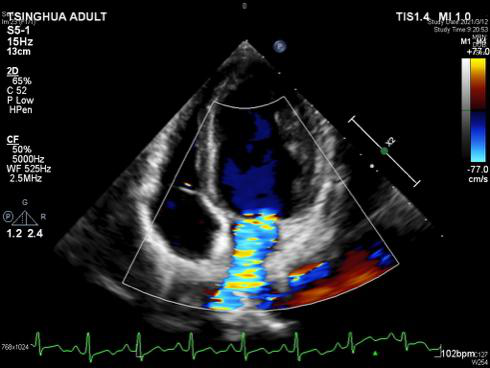

心脏超声显示二尖瓣大量反流

与预期一样,二尖瓣由于赘生物细菌的长时间侵蚀,薄薄的后叶瓣叶已经穿孔,前叶瓣缘也存在赘生物。为了保住二尖瓣,崔晓征用小圆刀在薄薄的瓣膜上进行了显微操作,沿着二尖瓣的前叶,轻轻地拨除附干净在上面的赘生物。拨除的“力道”非常重要:深一点就会损伤瓣膜,浅一点就会造成赘生物清除不彻底。凭借百分百的专注和游刃有余的手法,崔晓征成功剥离了前叶的赘生物,二尖瓣前叶不仅没有受到一点损伤,而且还较好地照顾了其脑部栓塞的情况。随后,他为洋洋切除了穿孔部分的二尖瓣,对后叶进行了环缩,心脏复跳后,超声显示仍存在少中量的反流。

按照术前计划,崔晓征的第一想法是保住洋洋的自己二尖瓣,尽量不使用机械瓣。可根据术中的实际情况,想保住二尖瓣是很难的,但考虑以后孩子要长期服药, 还有面临二次手术风险的可能。“我们还是尽量让他使用自己的瓣膜,不要给孩子留下遗憾!”这样的信念使得崔晓征再次打开洋洋的心脏,对二尖瓣进行了二次修复。心脏再次复跳后,超声显示瓣膜干干净净,反流几乎完全消失,洋洋的二尖瓣保住了!